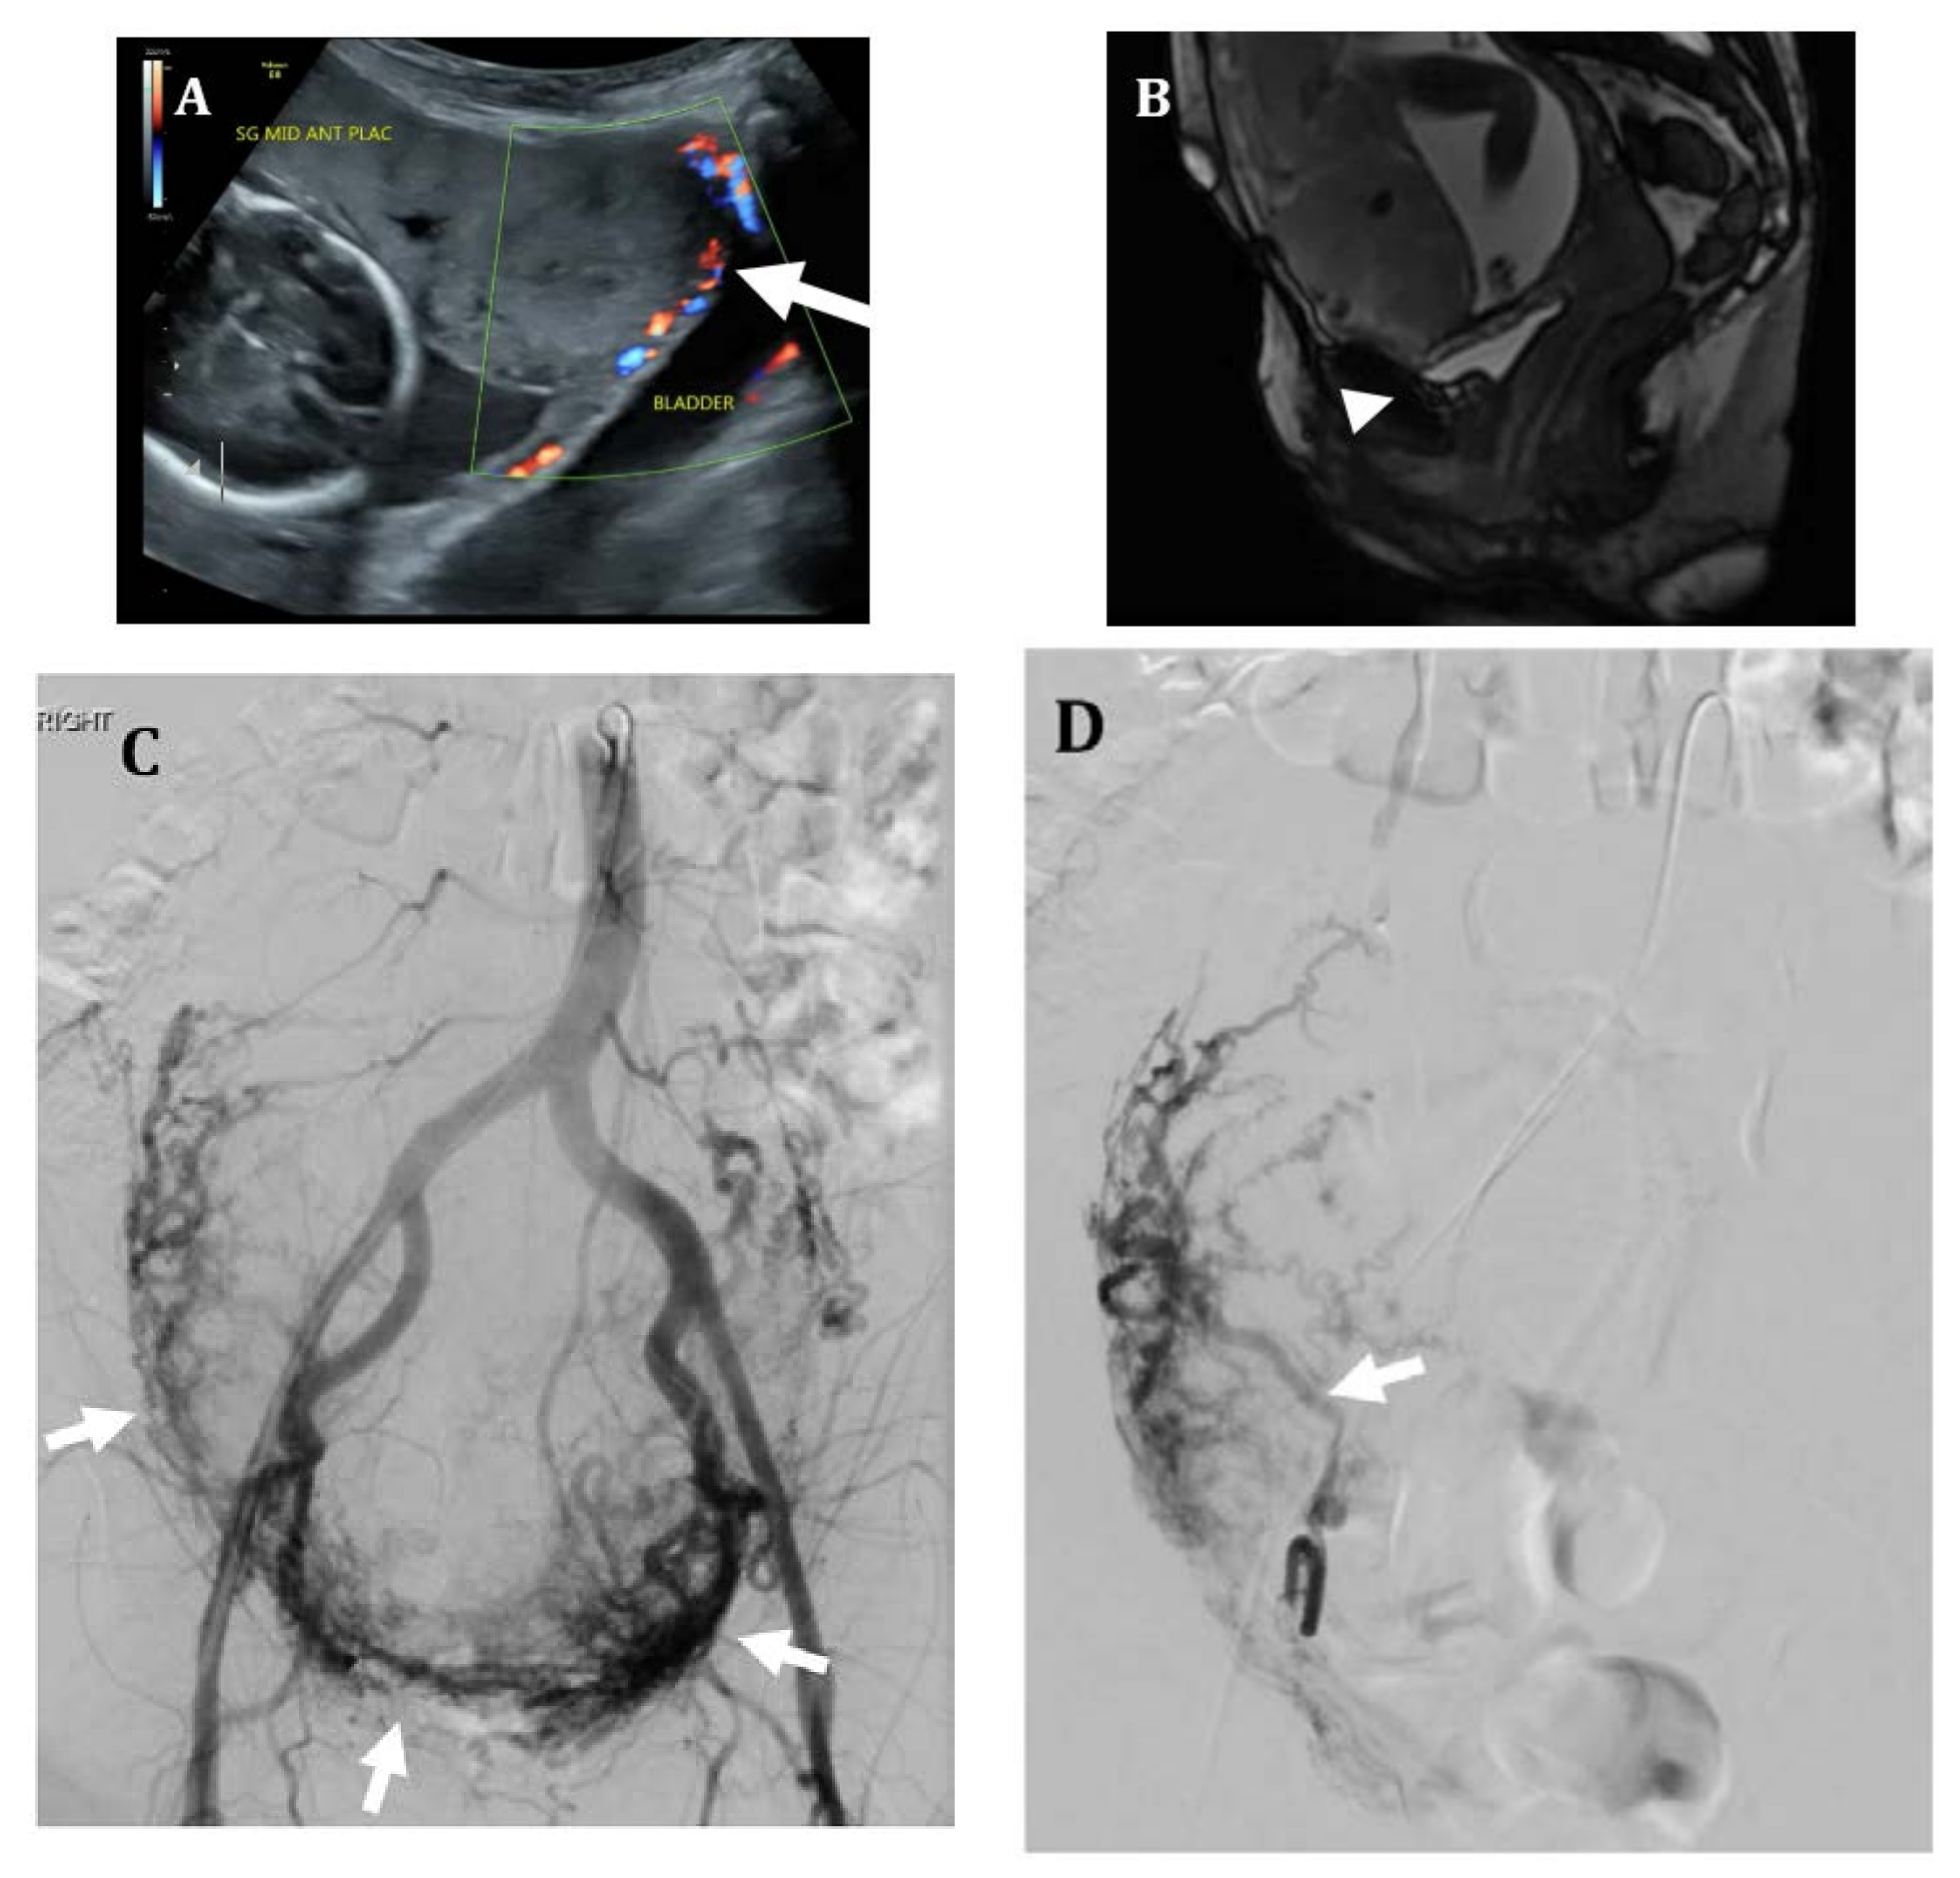

Figure 3.

Thirty-five-year-old female with placenta percreta. (A) Ultrasound at 19 weeks of gestation shows an abnormal placenta with multiple placental sonolucencies and focal bulging of placental tissue into the bladder (arrow). (B) Sagittal FIESTA MR image shows no discernable fat plane between placental tissue and bladder serosa (arrowhead), suspicious for bladder wall invasion. (C) Pre-hysterectomy pelvic angiogram shows a large hypervascular placenta (arrows). (D) Selective catheterization of the right uterine artery shows an enlarged right uterine artery (arrow) with marked placental hypervascularity. Embolization of bilateral uterine arteries was performed with 500–700-micron polyvinyl alcohol particles until stasis. (E) Due to concern for placental invasion of the bladder, the left vesicular artery was also selectively catheterized (arrow) and embolized using 500-micron polyvinyl alcohol particles. Bilateral internal iliac artery occlusion balloons were left in place. Patient ultimately underwent hysterotomy with delivery of a non-viable fetus at 22 weeks; hysterectomy was aborted due to significant pelvic side wall involvement. Patient has been subsequently followed with serial MR imaging for retained placenta.